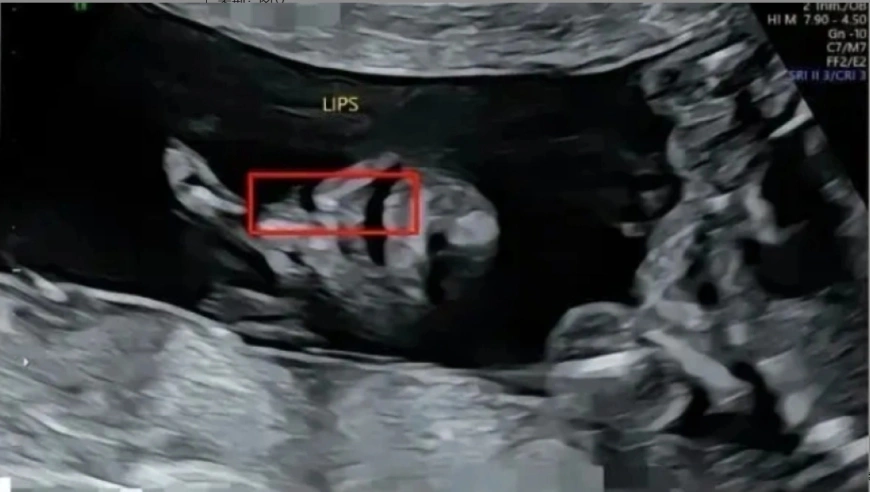

近日,广西桂林的胡女士抱着5个月大的婴儿到桂林市卫生健康委反映问题时,遭到工作人员粗暴对待一事引起全网热议。据此前媒体报道,因胡女士在桂林市妇幼保健院建档产检正常,但孩子出生后却被诊断为先天性单侧二度唇裂(左)、先天性单侧二度腭裂以及先天性牙槽嵴裂。在网上投诉后,胡女士又于7月21日到卫生健康委实地反映问题,但工作人员...